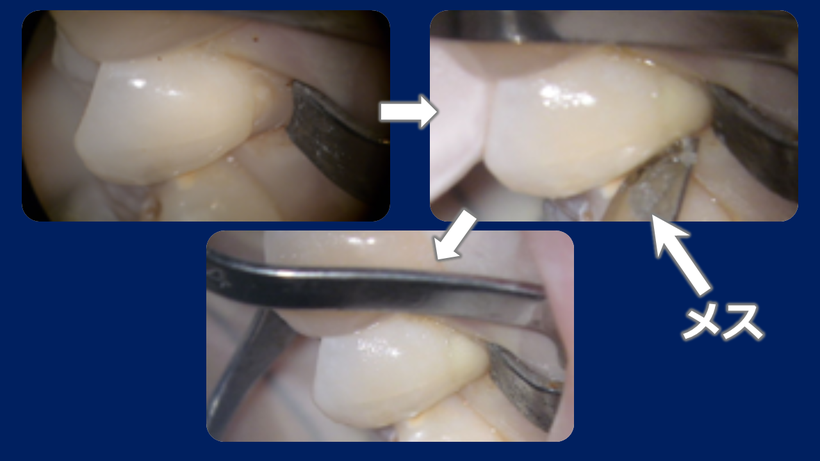

根元の虫歯治療を行う場合(WSDと呼ばれる歯の根元のを修復する時のラバーダム防湿)

WSD専用のラバーダムクランプをかけ、RIVA(GI)を充填、メスで形を整えます。